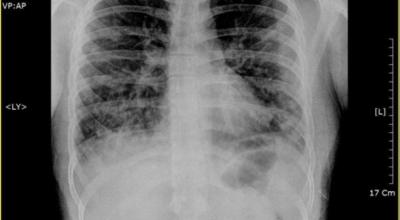

인체가 순조롭게 기능을 발휘하려면 폐 건강이 필수다. 폐는 인체가 효율적으로 움직이는 데 있어 바퀴 안에 있는 톱니 같은 역할을 하기 때문이예요. 산소를 제공하는 폐 기능이 감소하게되면 폐렴이나, 만성 폐쇄성 폐질환(COPD), 천식 등 정도가 심한 호흡기 질환 발생 위험이 증가해요. 이런 질병들은 폐를 공격해 숨쉬기 힘들게 만들어요.

특별히 현대 사회에서 폐는 가장 시달리는 장기 중 한 종류다. 가지가지 공해 성분으로 오염된 공기에 미세 먼지, 황사까지 더하면 폐 안쪽에 있는 허파꽈리(폐포)부터 정도가 심한 훼손을 입습니다. 따라서 폐 건강을 증진시키기 위하여는 폐에 좋은 음식을 섭취할 필요가 있어요.